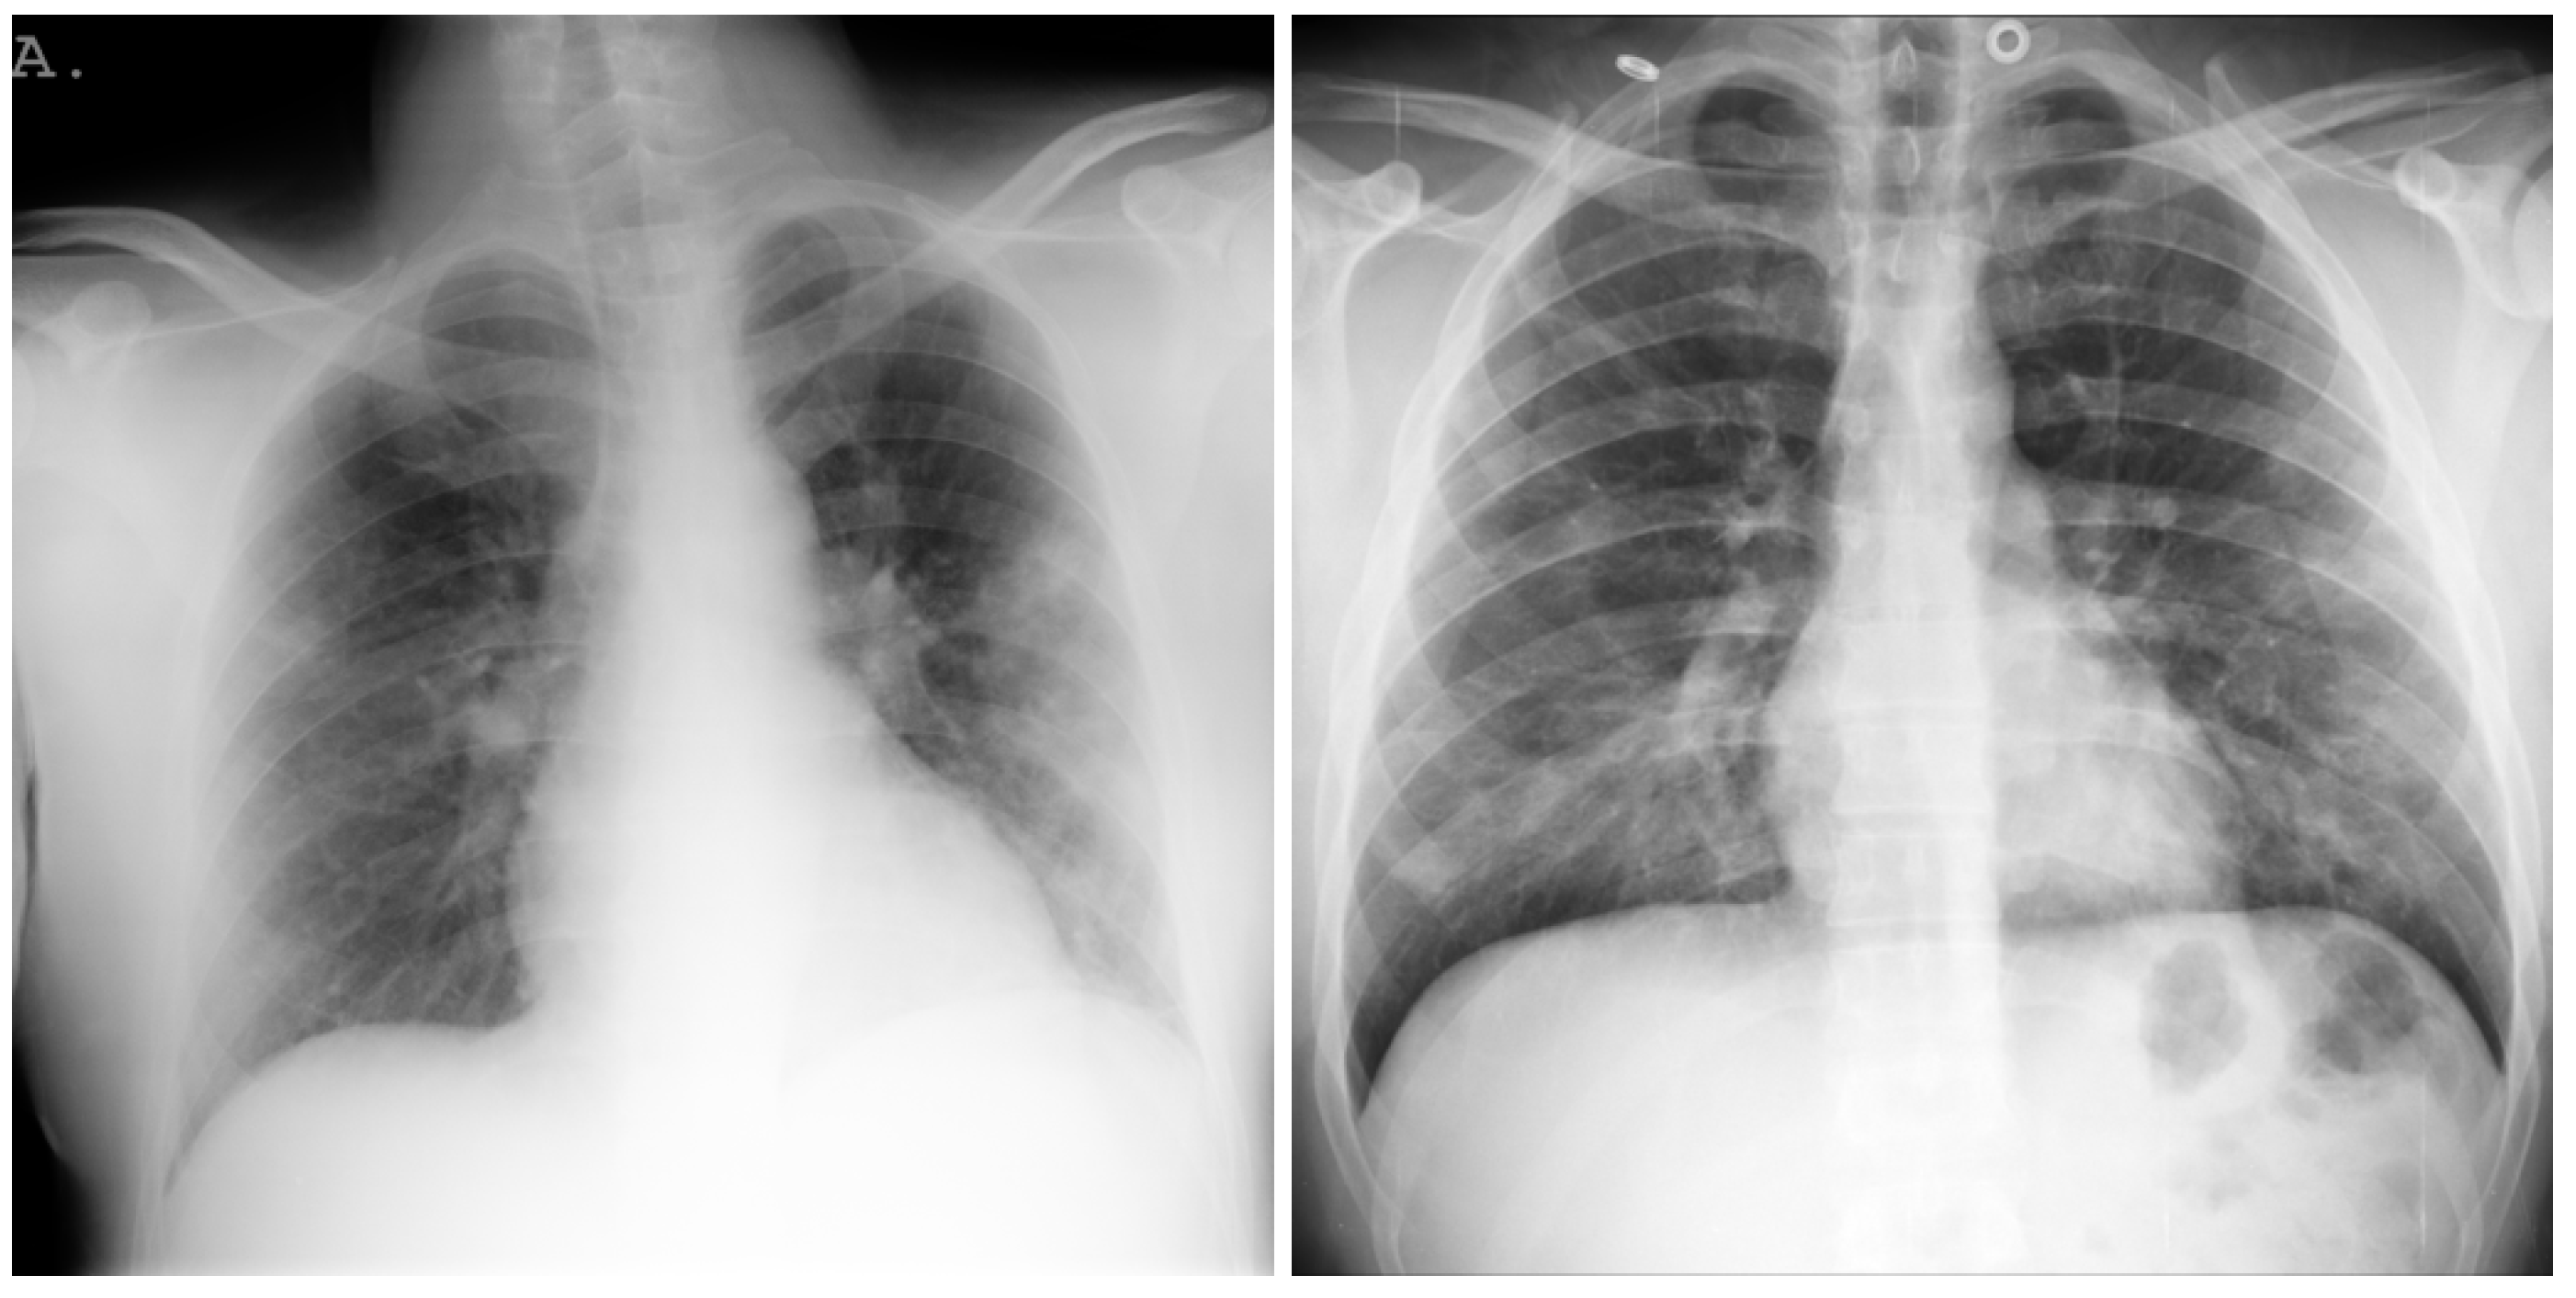

3.1. COVID-19 Image Data Collection (CIDC)

3.2. COVID-19 Radiography